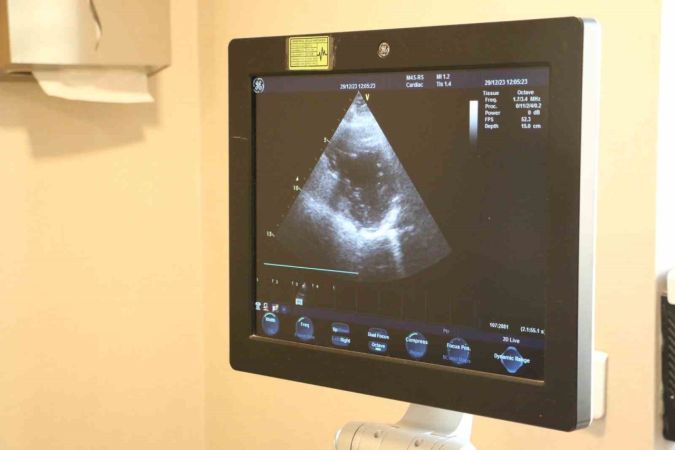

Kalp kapak hastalıkları, halsizlik, çabuk yorulma, nefes darlığı, ayaklarda şişlik, baş dönmesi ve baygınlık gibi belirtilerle kendini gösteriyor. Kardiyoloji Uzmanı Doktor Hüseyin Akçalı, bu hastalığın özellikle ileri yaşta sıkça karşılaşılan bir durum olduğunu belirtiyor. Düzenli tedavi edilmediğinde hayati risk taşıyan bu hastalık, yaşam standartlarını önemli ölçüde etkiliyor.